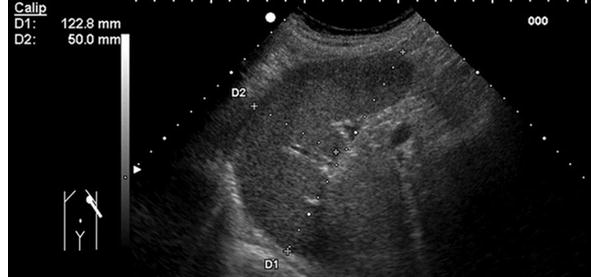

비장의 크기 측정

- 비장계수 (Splenic index, SI) ≥ 91 ㎠ (Grade 4 이상)

- 비장의 가장 긴 장축의 길이 ≥ 12 ㎝

- 초음파 한 화면을 넘을 경우 비장 비대 의심

비장 계수 구하는 방법 (Splenic index, SI)

- 비장이 폐에 의해 가려지는 것을 최소화하기 위해 Deep inspiration 동안 측정

- SI (cm²) = a(cm) × b(cm)

- a 는 비장의 최대 단면 영상에서의 가로 직경(transverse diameter), b 는 세로 직경(vertical diameter)을 의미